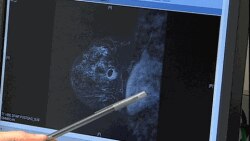

Yeni bir araştırmaya göre meme kanseri hastasının genetik bilgileri doktorların kemoterapi tedavisinin hasta üzerinde etkili olup olmayacağını tespit etmesinde yarar sağlıyor. Meme kanserinden her yıl milyonlarca kadın hayatını kaybediyor.

Meme kanseriyle mücadelede etkili tedavi ve önleyici ameliyat arasında seçim yapmak önemli bir karar. Yeni bir araştırmaya göre kanser hastasının genetik bilgileri kemoterapi tedavisinin en iyi yol olup olmadığına ışık tutuyor. Genetik bilgi şu anda da hastalığın önceden tahmin edilmesi ve önlenmesinde önemli rol oynuyor.

Özel bir araştırma şirketi olan Nuvera Biosciences'da bilimadamları yeni geliştirilen bir testin standart kemoterapinin hastanın yaşam şansını arttırıp arttırmayacağını gösterebildiğini söylüyor. Eğer kemoterapi işe yaramayacaksa hasta hemen başka alternatiflere yönlendirilebiliyor.

Araştırma, meme kanseri tedavisinin sonuçlarını ve kanserli kadınların hastalıktan kurtulma oranlarını inceliyor. 310 hastadan alınan tümör örneklerinin veri olarak kullanıldığı araştırmada hastalar iki ayrı kemoterapi ilacı ile tedavi edilmiş.

Araştırmacılar hastanın genetik bilgisinin, tümörün kemoterapiye yanıt verip vermediği ve hangi tümörün kemoya dayanıklı olduğu konusunda güvenilir kaynak oluşturduğunu söylüyor.